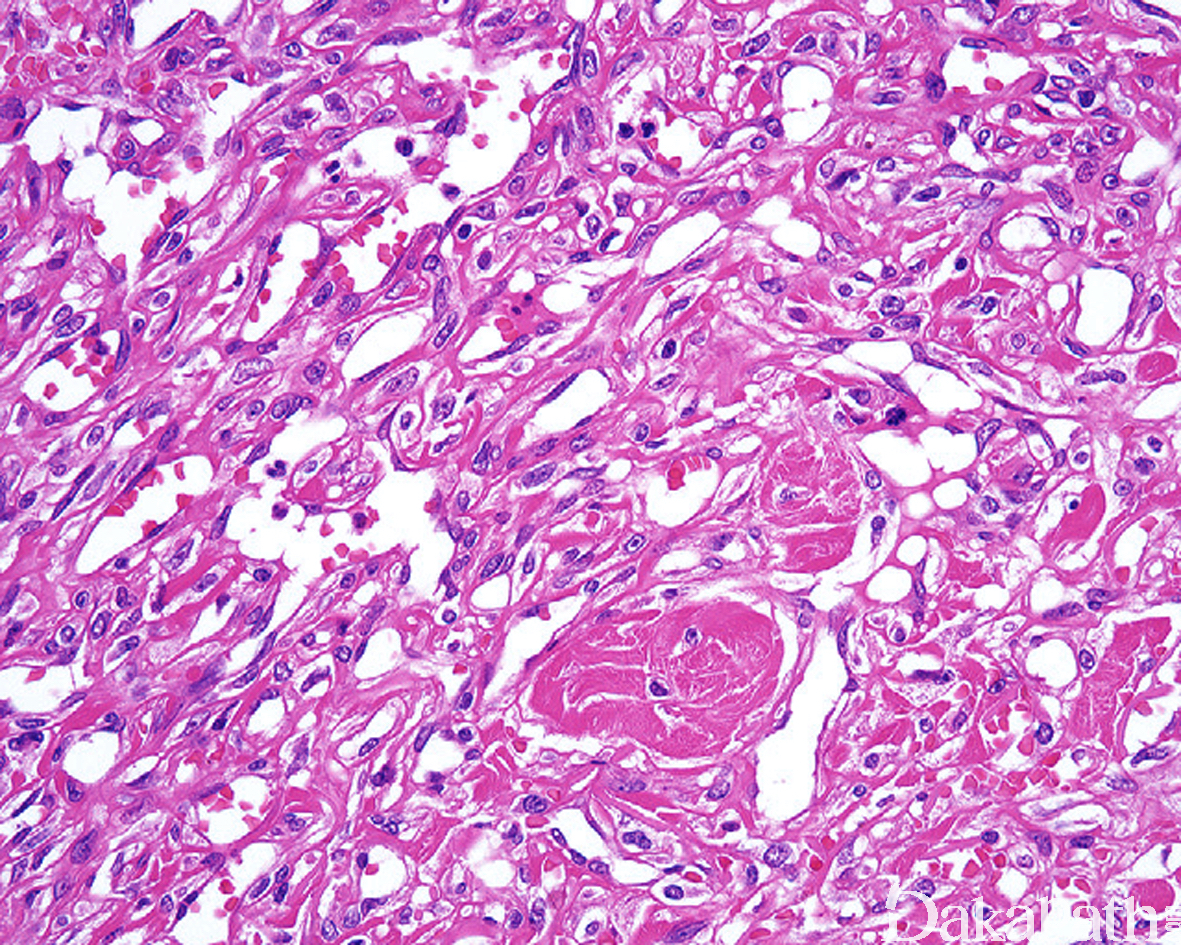

- 病变边界不清,主要累及真皮,偶见扩散入皮下组织内,由簇状增生的毛细血管组成,呈弥漫型、小叶状和弥漫-小叶混合型分布;

- 簇状增生的毛细血管排列紧密,内皮无明显的异型性,无复层内皮细胞增生表现,部分病例内皮可呈上皮样,内皮的周围均可见增生的周皮细胞;

- 少数病例中可见扩张的海绵状血管;

- 少数病例血管分割胶原纤维,但血管腔内无乳头状突起;

- 血管内常见纤维素性血栓形成,可伴机化,血管周围可见灶性的红细胞渗出;